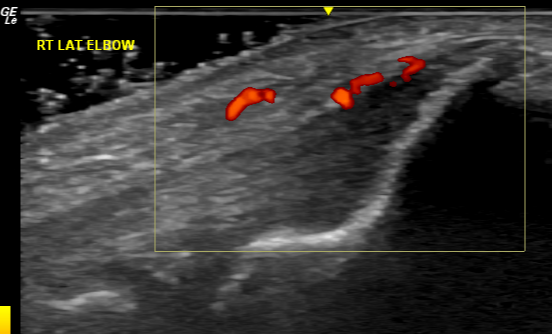

Fig 5b

Hey, Ultrasound! What Did I Do Without You?